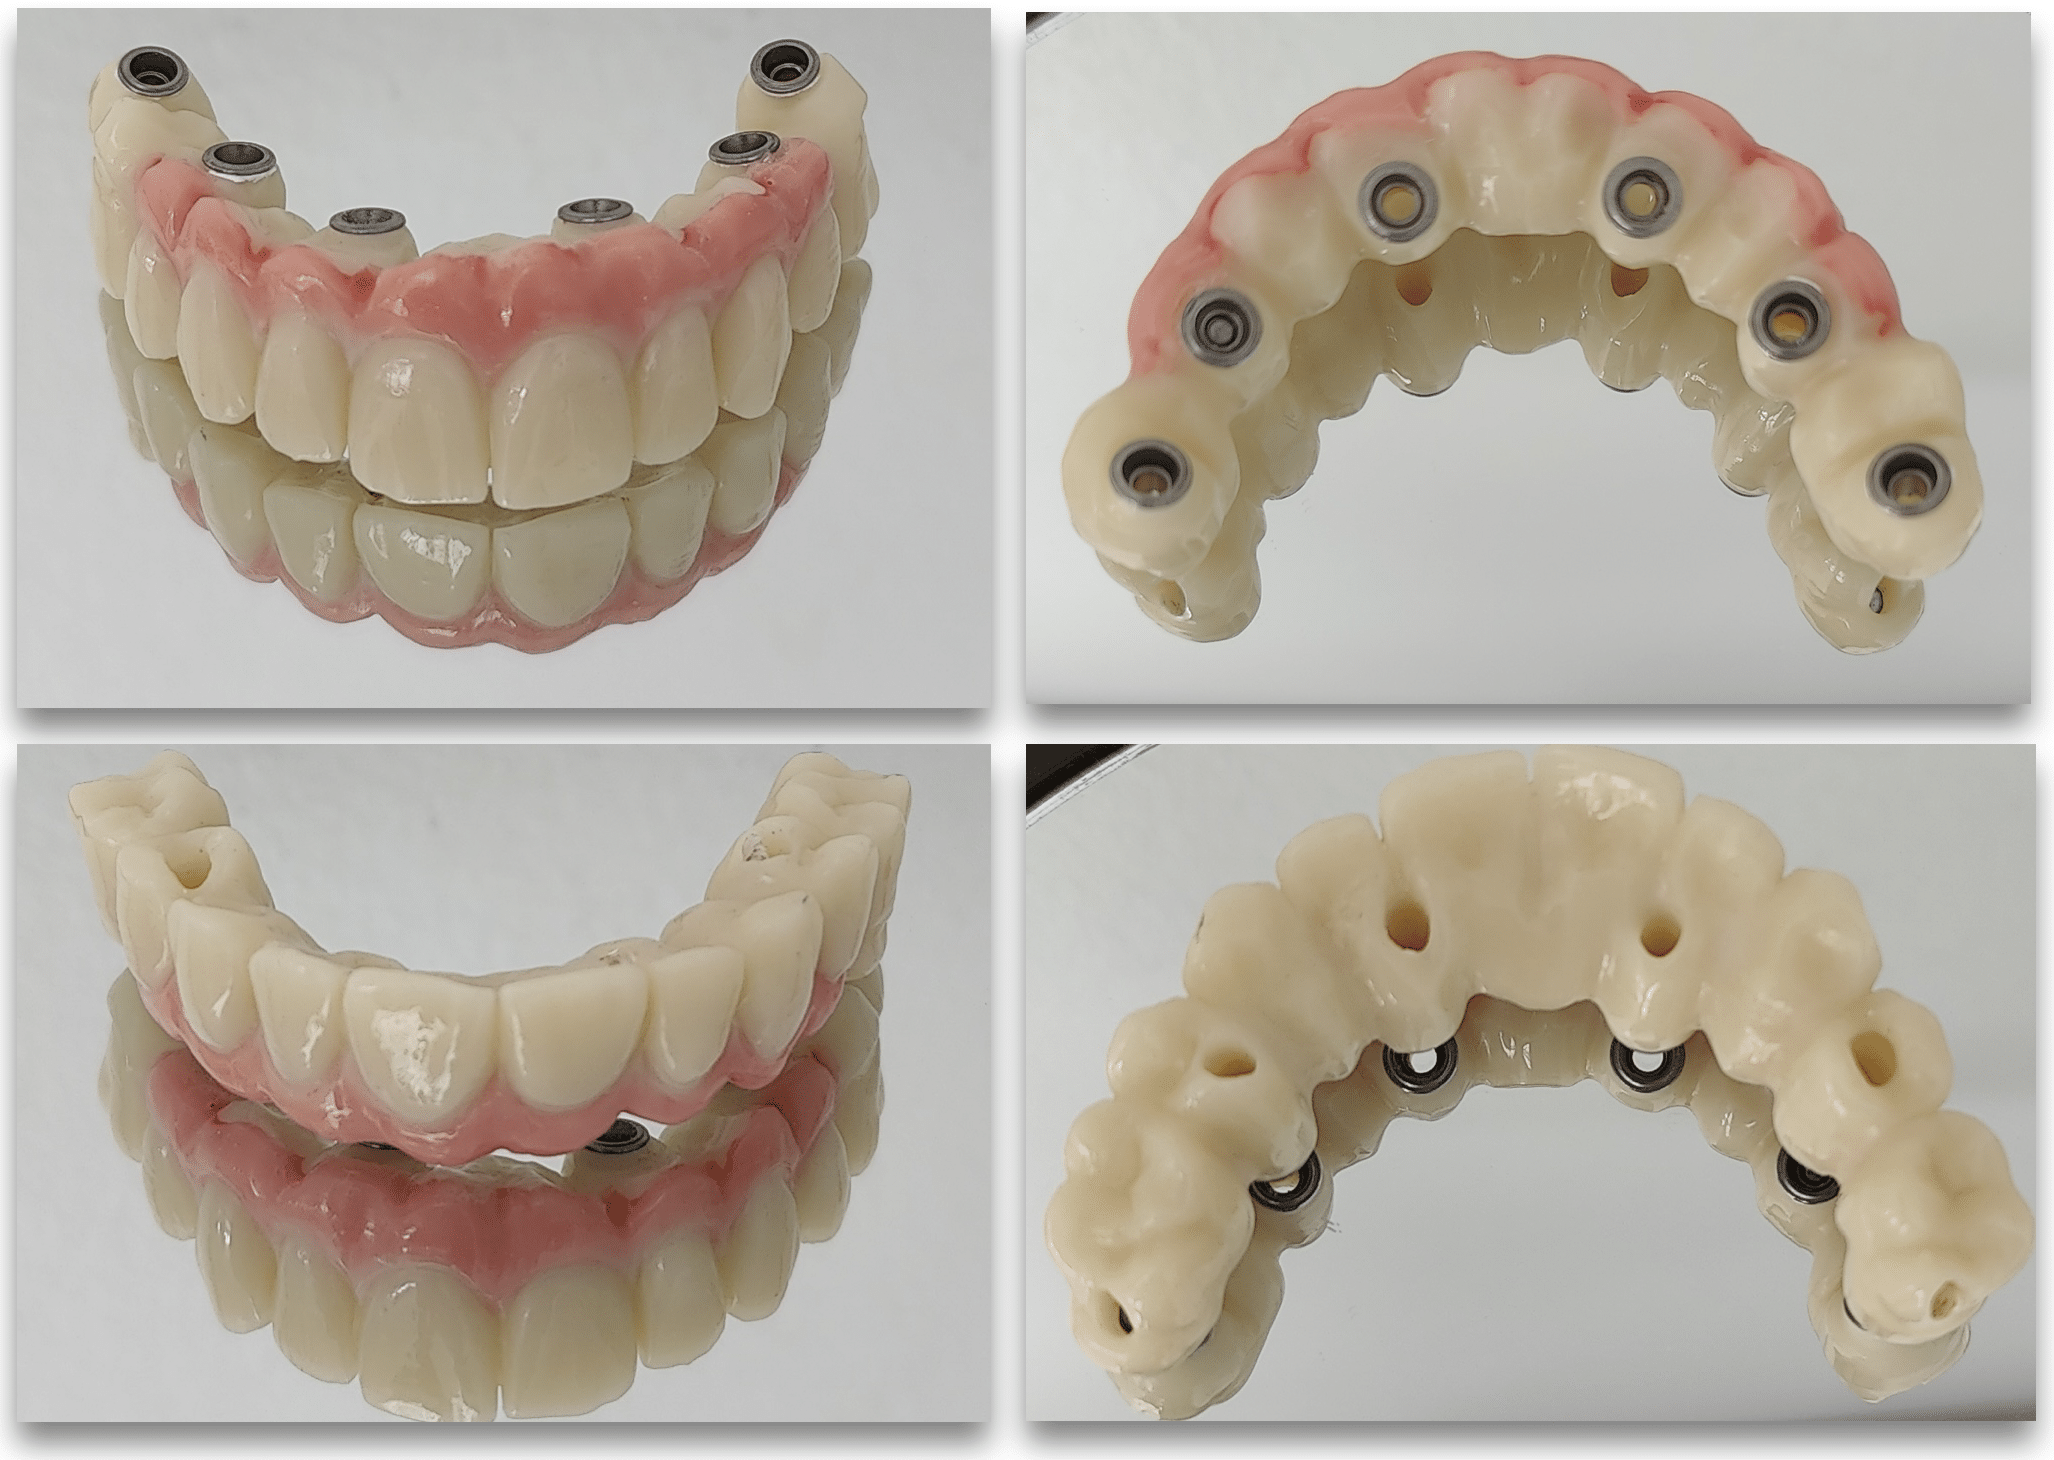

Bridge provisoire transvissé réalisé au laboratoire :

Ce bridge a été réalisé en technique d’impression numérique avec création de la fausse gencive par maquillage de surface